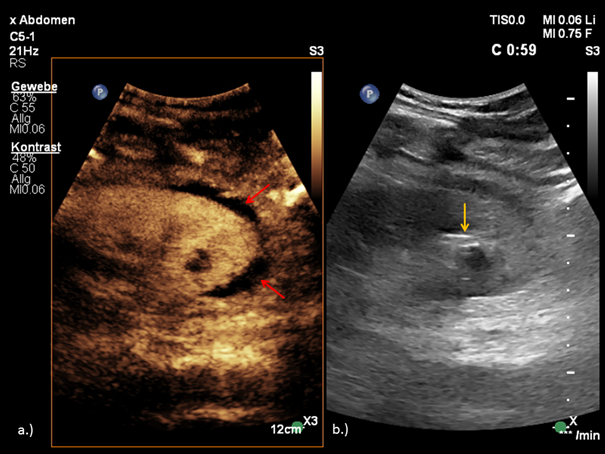

A baseline sonographic follow-up was performed, and depicted a hypo-anechoic lesion adjacent to the left kidney. (Figure 1)

Figure 1 Depiction of RAP as a cystic lesion (arrow).

The Color Doppler and Micro-flow Imaging examinations depicted a ying-yang swirling motion blood flow within the lesion. Because an active bleeding could not be excluded by color Doppler, the examination was complemented with CEUS. (Figure 2)